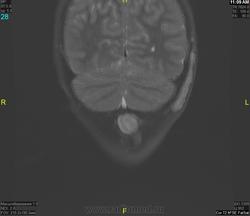

Уважаемые коллеги! Прошу консультативной помощи. Про пациента известно: девочка (7 лет), в анамнезе 2,5 года назад травма головы. Не диагностировалась. Периодически жалобы на болезненность при пальпации затылочной области(((((

Напоминает сосудистую структуру.Может, какая-нибудь лимфангиома?Видела на передней поверхности шеи, на задней - нет.

как будто связь с ликвором имеется.  Дополнил бы венографией, и FatSat"ом ну и контрастом, конечно.

Сегодня в ходе разговора с мамой девочки, выяснилось, что и у мамы есть подобное "образование". С ее слов, несколько лет назад ей делали пункцию для исключения онкологии. Результат пункции: содержится нервная ткань и лимфоциты ( опять же никаких документов я не видела). То есть можно говорить о наследственном характере.

Нейрофиброма вполне может быть. Плексиформная. Проверить на нейрофиброматоз. Я видел такой же структуры и локализации. Пятен на коже нет? Вообще на теле? И нет ли чего похожего в позадиглоточном пространстве?

есть похожее образование в позадиглоточном пространстве)

многоузловое образование  исходящее из задней части предпозвоночного пространства с переходом на подкожную жировую клетчатку головы!шваннома ,нейрофиброма и их злокачественные аналоги